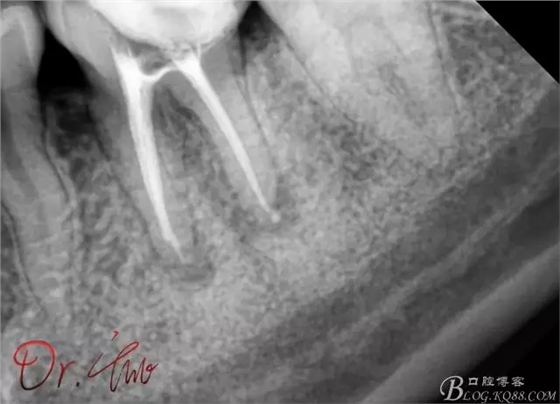

試主尖,近中頰側(cè)試主尖,此時手用銼02錐度的已擴到30號,可以明顯感覺到臺階位置,挫預(yù)彎后找好正確位置可順利到達根尖,但是機用銼就是下不去,也是郁悶

試主尖,在30號02錐度K挫到達根尖后,用02錐度牙膠尖找準位置,進行試尖

最后根充,明顯可看到臺階位置,期待預(yù)后效果